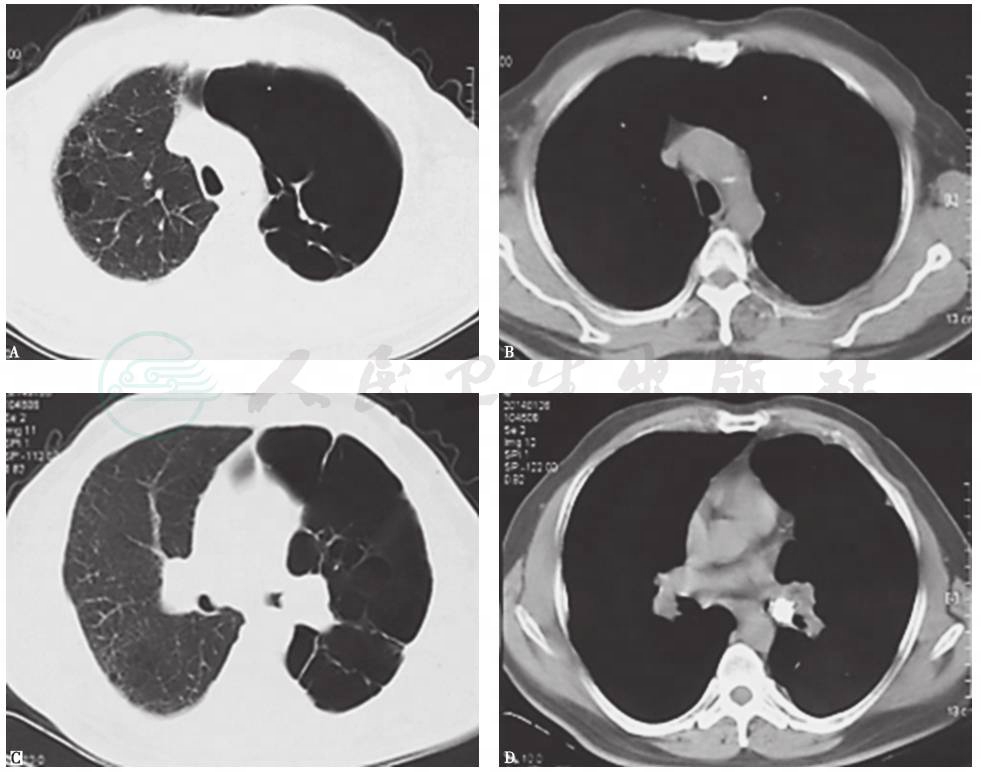

入院1个月前,胸部CT见左侧多发肺大疱,左下肺脓肿,其内见液平,左主支气管腔内高密度影,左侧少量胸腔积液(图1),抗感染治疗后未见好转(图2)。

图2 抗感染治疗后复查胸部CT表现

近13年来,患者胸部X线和CT均表现为左肺从初始体积大致正常,逐渐出现左肺体积减小,肺实质高密度影肺炎样改变;随着病情发展出现多发肺大疱、肺脓肿和肺毁损(图3~图10),并见左主支气管内病灶逐渐增大,最终导致管腔闭塞。

图4 10年半前胸部CT表现

胸部CT可见左主支气管被高密度钙化灶不全阻塞,左肺体积缩小,但透过度略有增高,同时伴左侧胸膜弥漫性增厚

图7 6年半前胸部CT表现

胸部CT可见左主支气管被高密度钙化灶阻塞进一步加重,但左上肺体积增大含气增多,左下肺略缩小伴局限性斑片状高密度病灶和膨胀不全;右肺代偿性含气增多;左侧胸膜弥漫性病变减轻

图8 4年半前胸部CT表现

胸部CT可见左主支气管被高密度钙化灶阻塞进一步加重,管腔几近完全阻塞,左肺体积略缩小伴局限性不张,左上肺代偿性肺气肿和肺大疱进一步加重;右肺代偿性含气增多;未见左侧胸膜病变

图9 2年半前胸部CT表现

胸部CT可见左主支气管被高密度钙化灶管腔几近完全阻塞,左上肺代偿性肺气肿和肺大疱进一步加重,左下肺体积略增大伴多发肺大疱,并见左下肺前内基底段实变;右肺代偿性含气较前有所减轻

图10 1年前胸部CT表现

胸部CT可见左主支气管病灶同前,左上肺代偿性肺气肿和肺大疱进一步加重,左下肺多发肺大疱增多,左下肺前内基底段实变仍存在;右肺代偿性含气未见加重